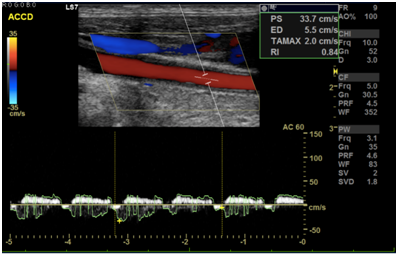

Cranioencephalic computerized tomography excluded acute ischemic lesions.CDS revealed severe stenosis of the innominate artery (PS 38 cm/s) (Figure 1), occlusion of right vertebral artery, total flow inversion of the right internal carotid artery (ICA) (Figure 2), partial endosystolic flow inversion of right CCA (Figure 3) and low amplitude anterograde flow of right external carotid artery, no significant lesions were found on the left carotid axis. Computerized tomography angiography (CTA) excluded significant carotid lesions and revealed pre-occlusive stenosis of the innominate artery by a calcic lesion (Figure 4).Surgical approach consisted of ultrasound-guided puncture of right brachial artery and surgical exposure of right CCA. Brain protection was achieved by direct clamping of the common carotid artery and subsequently carotid and axillary retrograde endovascular access was obtained. Placement of 6F introducer on brachial artery and 8F on right CCA (Figure 5). After pre-dilatation with a 4x40mm balloon (Admiral Xtreme™, Medtronic), a kissing stent technique was performed with a 6x59mm covered stent (AdvantaV12™, Getinge) on the right CCA and 7x57mm balloon-expandable stent (Visi-Pro™, Medtronic) on the right subclavian artery. At the end of the procedure direct expulsion of eventual embolic material was performed prior to declamping and a good permeability of the revascularized arteries was verified (Figure 6). Clamping time was under 1minute. The postoperative period was uneventful and patient was discharged 3days later.

Figure 1 Stenosis of the innominate artery.